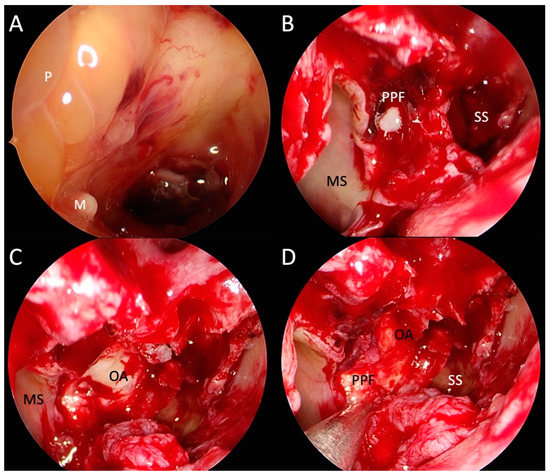

2. Case Presentation

2.2. Revisional Treatment